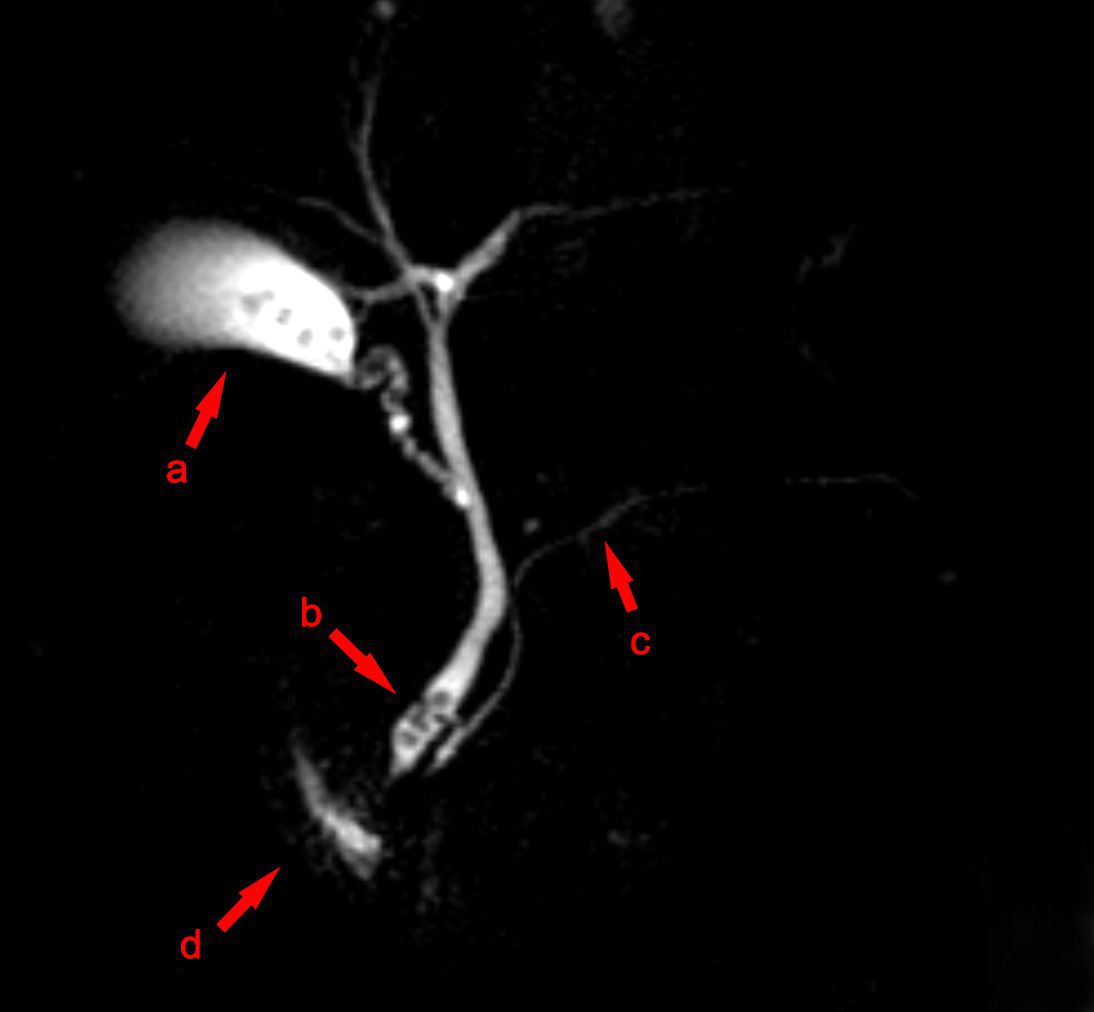

MRCP is a type of magnetic resonance imaging that is non-invasive in nature and is used to visualise the intra and extrahepatic biliary tree and the ductal system of pancreas. This technique uses the fluid which is present in the biliary and pancreatic ducts as an intrinsic contrast medium resulting in acquisition of images using sequences that are heavily T2 weighted. MRCP is indicated in several conditions of the pancreaticobiliary ductal system and is usually preferred over ERCP when invasiveness is to be avoided.